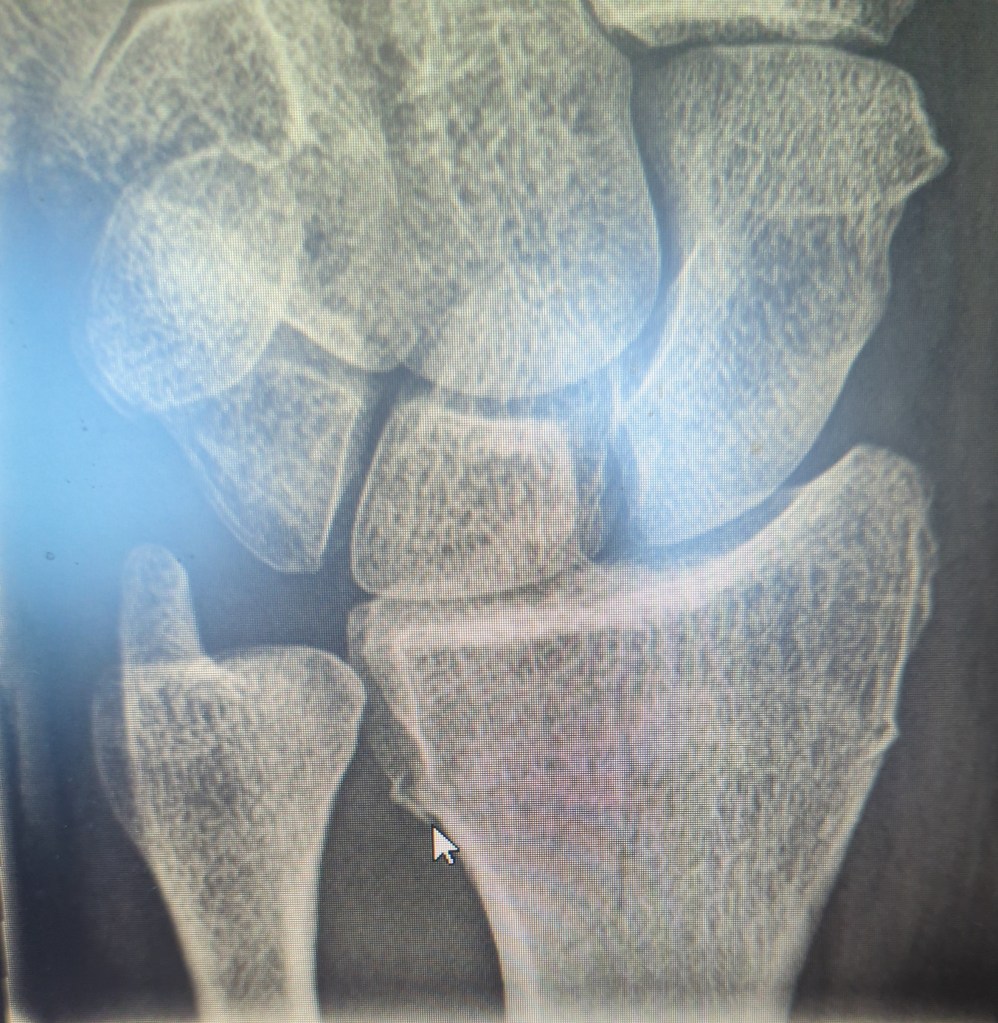

On Monday the 22nd I had the x-ray above which shows a transverse distal radius fracture. No surgery, but I’ll have a cast until October 14.